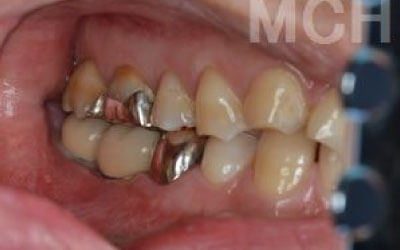

歯が抜けてそのままにしたら他の歯がズレてしまいました。どうしたらよいでしょう?

軽いズレなら調整や詰め物で対応できますが、大きく傾いた場合は矯正や被せ物が必要です。ズレが広がる前に早めの診査・治療をおすすめします。

多少の位置のズレであれば、噛み合わせの調整や小さい詰め物で調整することも出来ます。

ただ、抜けてから数年が経って大きく傾いた歯は歯並び矯正をするか、 歯を大きく削ってかぶせ物をする必要があります。

2 歯が傾いてくる、落ちてくる

歯の位置は互いに支え合ってバランスを保っています。 つまり、歯が抜けることによって支えが無くなり抜けた部分の両隣の歯が倒れたり、 上の歯が下がってきたりします。